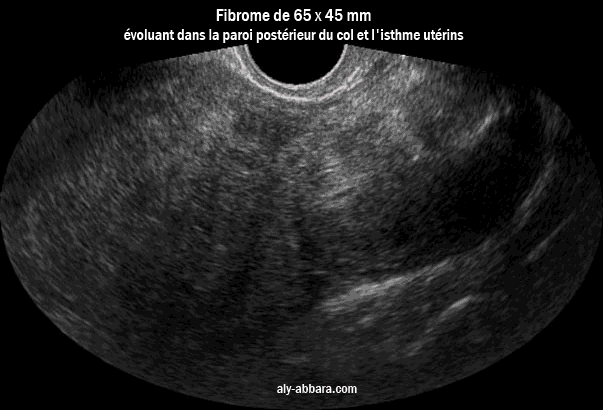

Image échographique montrant un myome se développant au niveau de la paroi postéieure du col utérin et l'isthme